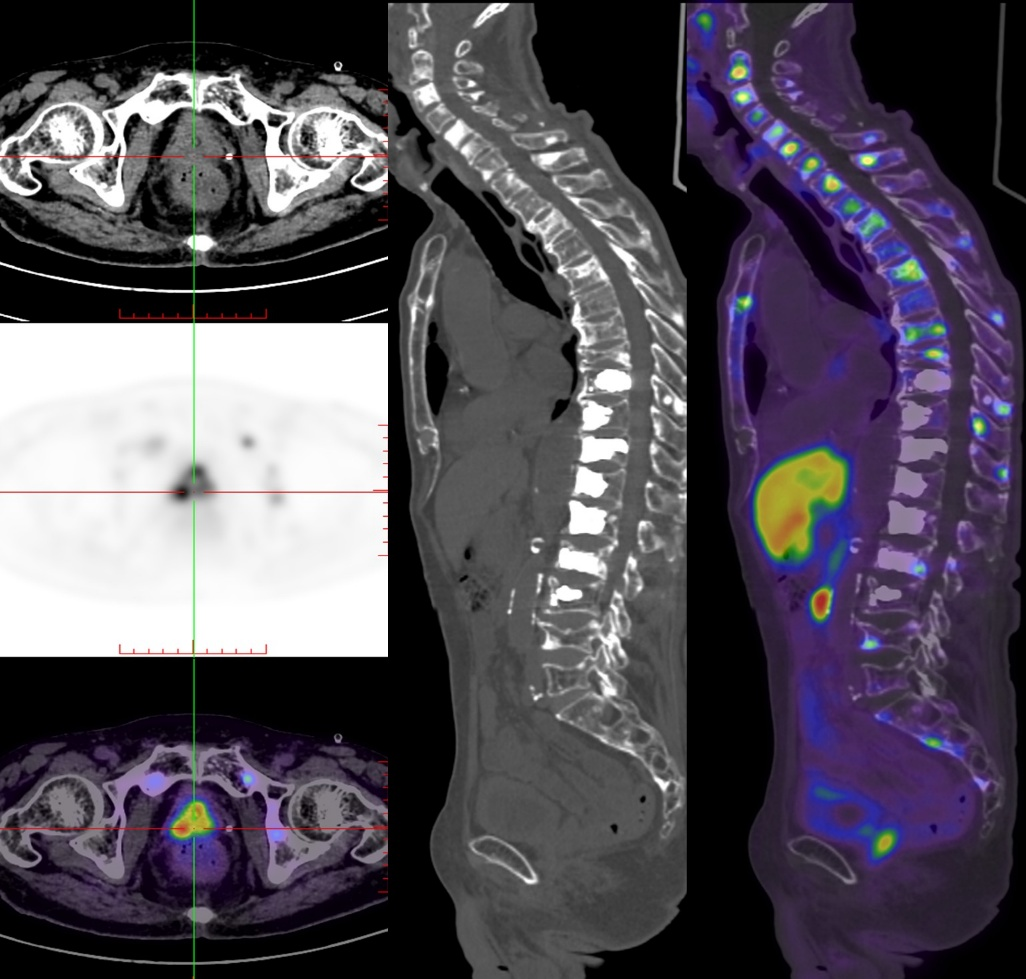

泌尿外科学科带头人、副院长王建宁教授团队全面评估后,安排患者行PSMA-PET/CT检查,提示全身多处骨转移灶呈现PSMA高表达;基于这一精准诊断,王建宁教授团队迅速召开多学科会诊,综合评估患者满足¹⁷⁷Lu-PSMA放射性配体治疗适应症,随即为该患者量身制订了个性化精准诊疗方案,并顺利完成此次治疗。

“这项治疗就像给癌细胞‘精准点穴’。”王建宁教授形象地解释道,“它利用前列腺特异性膜抗原(PSMA)作为‘分子靶点’,通过特异性配体这一‘导航系统’,将放射性核素¹⁷⁷Lu精准送达肿瘤细胞——β射线破坏癌细胞DNA实现杀伤,γ射线则同步显像,真正实现‘治疗+显像’一体化。”相比传统化疗或内分泌治疗,¹⁷⁷Lu-PSMA放射性配体治疗对常规治疗无效的晚期前列腺癌患者具有显著优势:临床缓解率更高,副作用可控。其射线穿透深度仅毫米级,对正常组织及周围环境的辐射影响极小,安全性高。